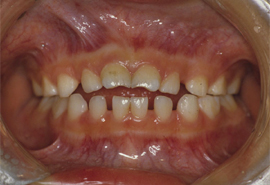

(2)開咬:上下の前歯の間に隙間があく。

![]() |

【写真2】 6歳児の親指しゃぶりによる開口。上下の前歯が咬み合っていない。 |